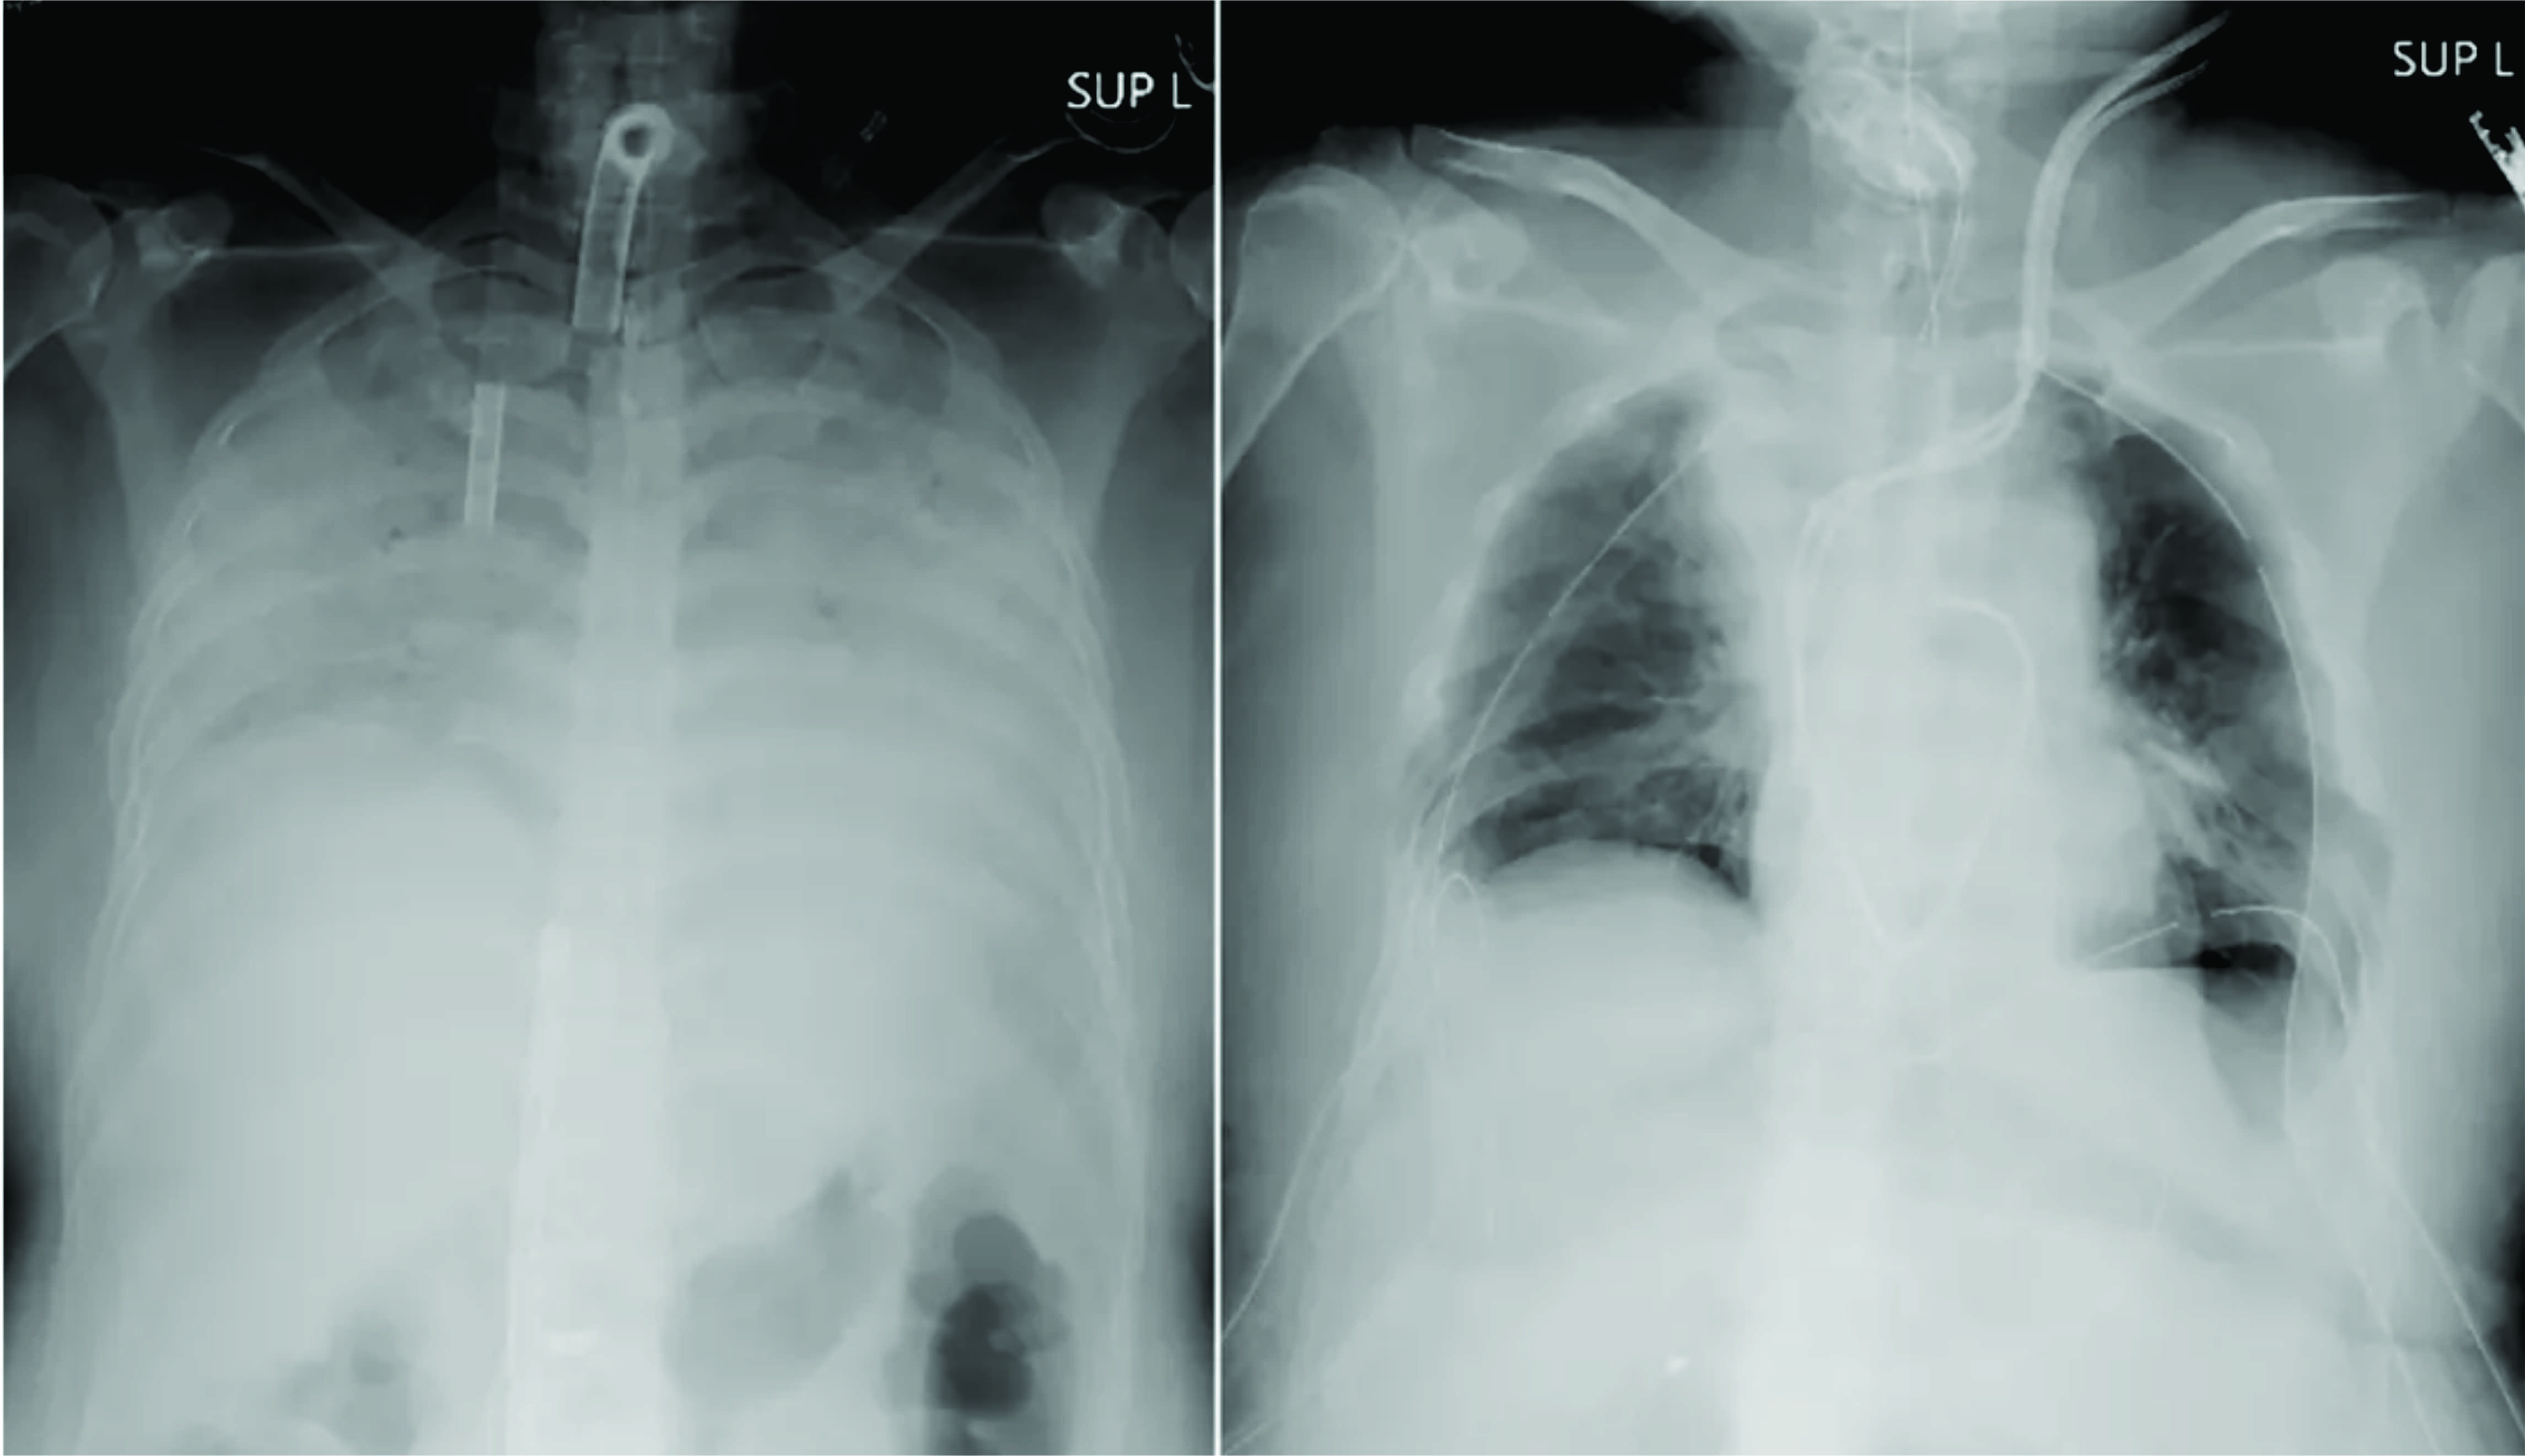

Paciente com Covid-19 recebe transplante de pulmão de doadores vivos

Japoneses anunciaram o 1º transplante mundial de tecido pulmonar de doadores vivos para uma paciente com grave lesão pulmonar causada pelo novo coronavírus.